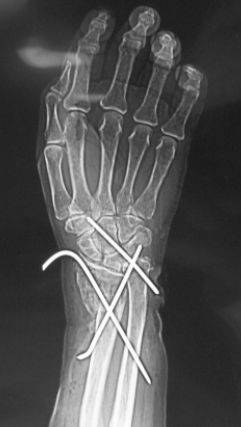

患者王某,老年女性,80岁,主因摔伤致左腕开放性骨折急症于2010年3月入院。查体:患者左侧腕关节处尺骨茎突哆出,掌侧皮肤裂伤,长约6cm,肌腱及皮下组织外露,左腕关节畸形。入院诊断为左侧腕关节开放伤(图1a);左侧桡骨远端骨折;左侧腕关节脱位(图1b)。于入院当日急症臂丛麻醉下行左腕伤口清创缝合术,左侧尺腕关节复位内固定术,左侧桡骨远端骨折复位内固定术(图2)。手术过程顺利,术后患者恢复良好,约术后5周拔除左侧腕关节固定克氏针,后患者自动出院。出院后1日患者因突发喘憋,进行性加重再次就诊于我院,血气分析示PO2 36.3mmHg,PCO2 30.4mmHg,D-二聚体4000ng/ml,胸CT示左下肺大片高密度影,肺通气灌注扫描显像提示双肺多发节段灌注缺损。入院诊断为:I型呼吸衰竭;肺栓塞;冠心病;高血压病3级;糖尿病2型;左桡骨远端骨折。给予速碧林 4100IU/d经验性抗凝治疗。第2日患者喘憋症状明显缓解,自诉无呼吸困难,动脉氧分压升至141mmHg(鼻导管吸氧5L/分)。应用速碧林3日后加用华法令5mg /d,间断复查KPTT及INR,华法令与速碧林重叠应用5日后,患者PT延长至18.9s,即停用速碧林,单独应用华法令,1周后患者好转出院。

图2 患者术后X线片。